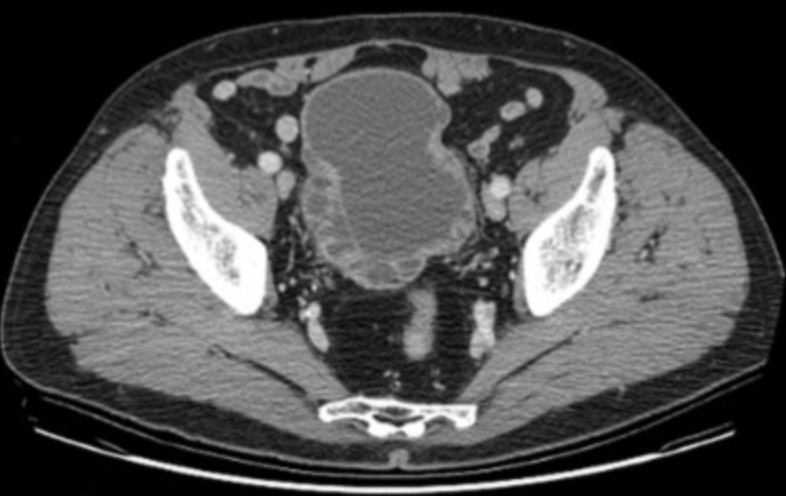

Bladder Rupture

• Comes in two flavors - intra-peritoneal & extra-peritoneal

• Extra-peritoneal bladder rupture

• Much more common, ~ 90% of cases

• Result of trauma (pelvic fractures), sometimes after instrumentation/procedures

• Look for contrast pretty much anywhere other than between bowel loops

• Treatment = foley catheter

• Intra-peritoneal bladder rupture

• Less common, ~10% of cases

• Result of direct blow to a distended bladder

• Rupture typically at dome of bladder

• Look for contrast in between bowel loops or at paracolic gutters

• Treatment = surgery